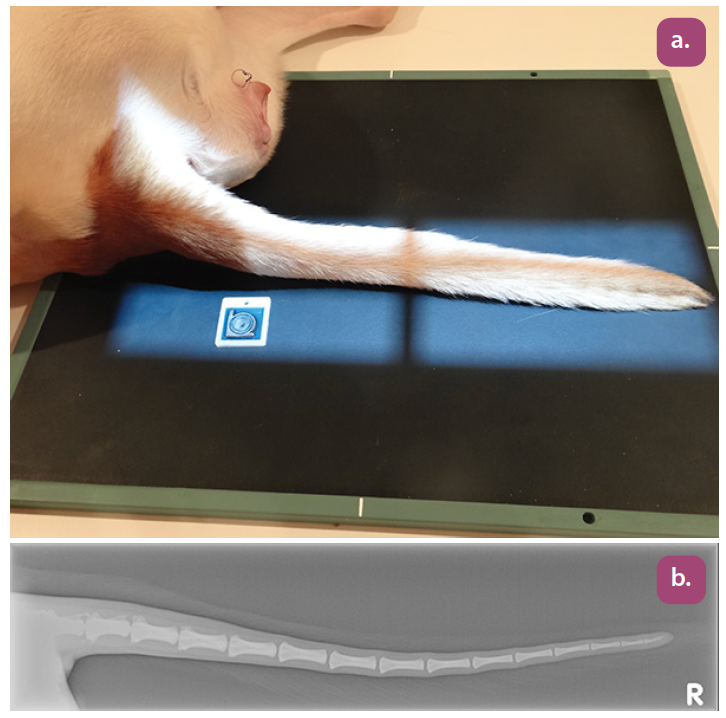

lateral coccygeal spine projection